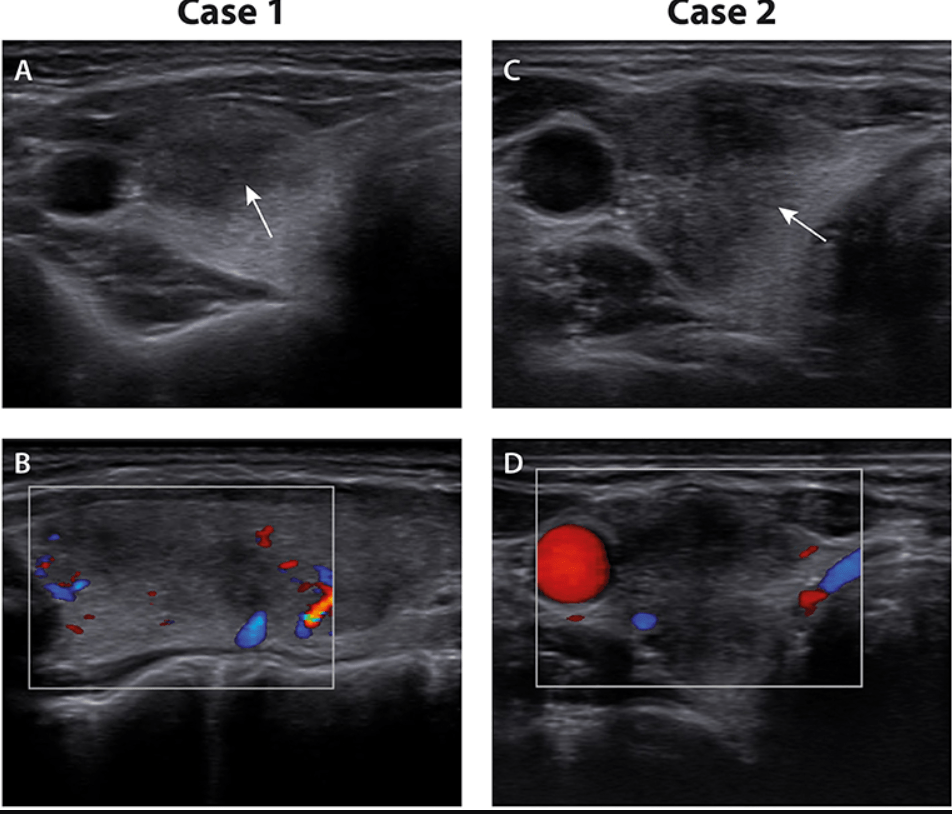

Autre exemple, autre organe: une femme 49ans déclenche une thyroidite dans les 2 semaines après sa dose de Moderna. Une aspiration d’un nodule thyroidien donne des lymphocytes, des marcophages et des cellules géantes multinucléées …

Case Report: Two Cases of Subacute Thyroiditis Following SARS-CoV-2 VaccinationSubacute thyroiditis is an inflammatory thyroid disorder associated with viral infections. Rare cases of subacute thyroiditis have also been described following vaccination. Recently, a few cases of s…https://www.frontiersin.org/articles/10.3389/fmed.2021.737142/full